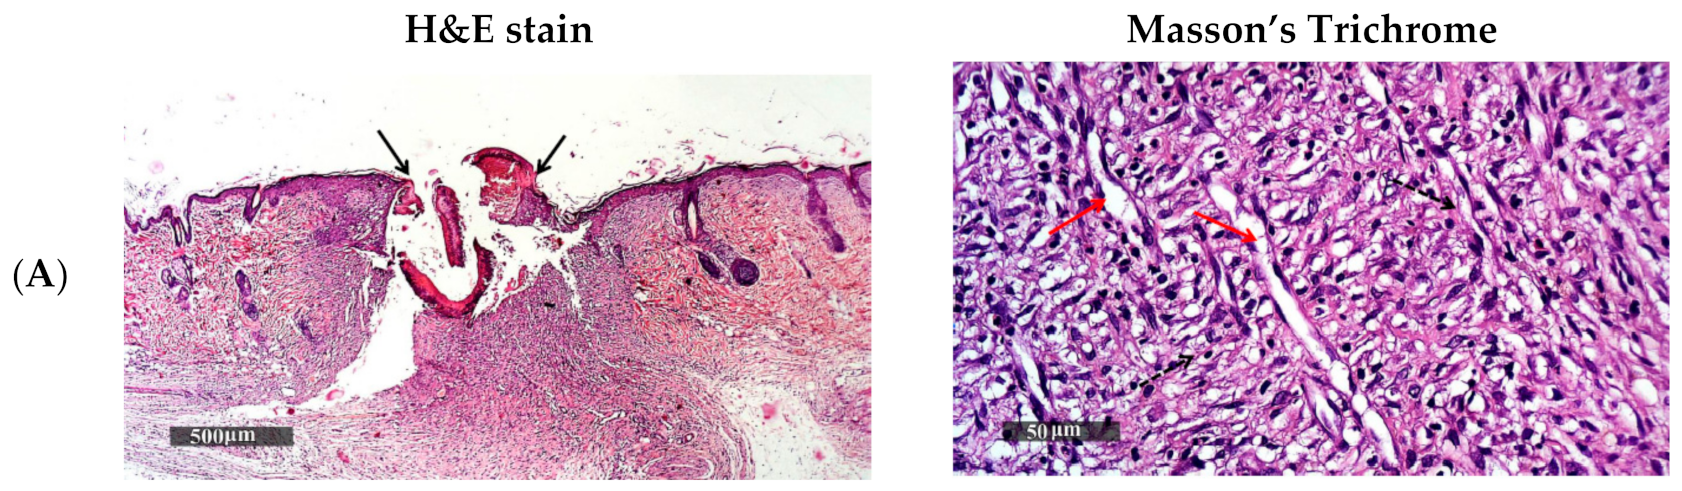

3.5.2. Histopathological Study

Light microscopic examination of the histopathological sections of the rats stained with H and E and Masson’s trichrome for the four groups after 15 days of the wound induction and a normal control sample are illustrated in Figure 10. The untreated group (A) (Figure 10A) showed persistence of epidermal loss and ulceration as presented even after 14 days of treatment, with adjacent sub epidermal hemorrhagic patches and high cellular granulation tissue formation rich with inflammatory cells infiltrates filling the wound gap and non-organized dermal collagen deposition (dashed arrow) which was significantly (p = 2.28 × 10−13) lower than the normal control sample, indicating an incomplete process of healing [40].

Figure 10.

Histopathological microscopical examination section of the non-treated control group (A); treated group with NVH suspension (B); treated group with blank chitosomal formulation (C) and treated group with NVH-loaded chitosomal formulation (D), and normal control sample skin (E).

Concerning the treated groups, the group treated daily with NVH suspension (B) showed still persistence focal epidermal loss and incomplete re-epithelialization as presented in Figure 10B with the black arrow with focal subepidermal hemorrhagic patches. The wound gap was replaced with cellular granulation tissue with mild inflammatory cells infiltrates and minimal organized collagen fibers formation as presented with the dashed arrow (p = 5.25 × 10−8). This could be due to the presence of NVH, and resulting in a high concentration of NO causing endothelium-dependent vasodilatation, leading to stimulation of inflammatory cells and proliferation and closure of wound at a faster rate [11]. Group C (Figure 10C) treated with the blank chitosomes showed complete epidermal re-epithelization and wound closure as presented by the black arrow, also accompanied with focal subepidermal hemorrhagic patches. There were more collagen-rich dermal granulation tissue samples presented by the dashed arrows (p = 6.5 × 10−5), with high cellular infiltrates and newly formed blood vessels (red arrow) due to the presence of chitosan [58,111,112,114].

On the other hand, the microscopical examination of the group treated with NVH-loaded chitosomes F6 (D) [depicted in Figure 10D] revealed a more accelerated wound healing process with complete epidermal re-epithelization as presented by the black arrow. The wound gap was reduced and filled with fibrous granulation tissue and high records of mature collagen bundles (dashed arrow), which was not significantly (p = 0.243) different from the collagen bundles present in the normal control group (Figure 10E) represented by the star, showing its superiority in aiding the wound healing and tissue regeneration.